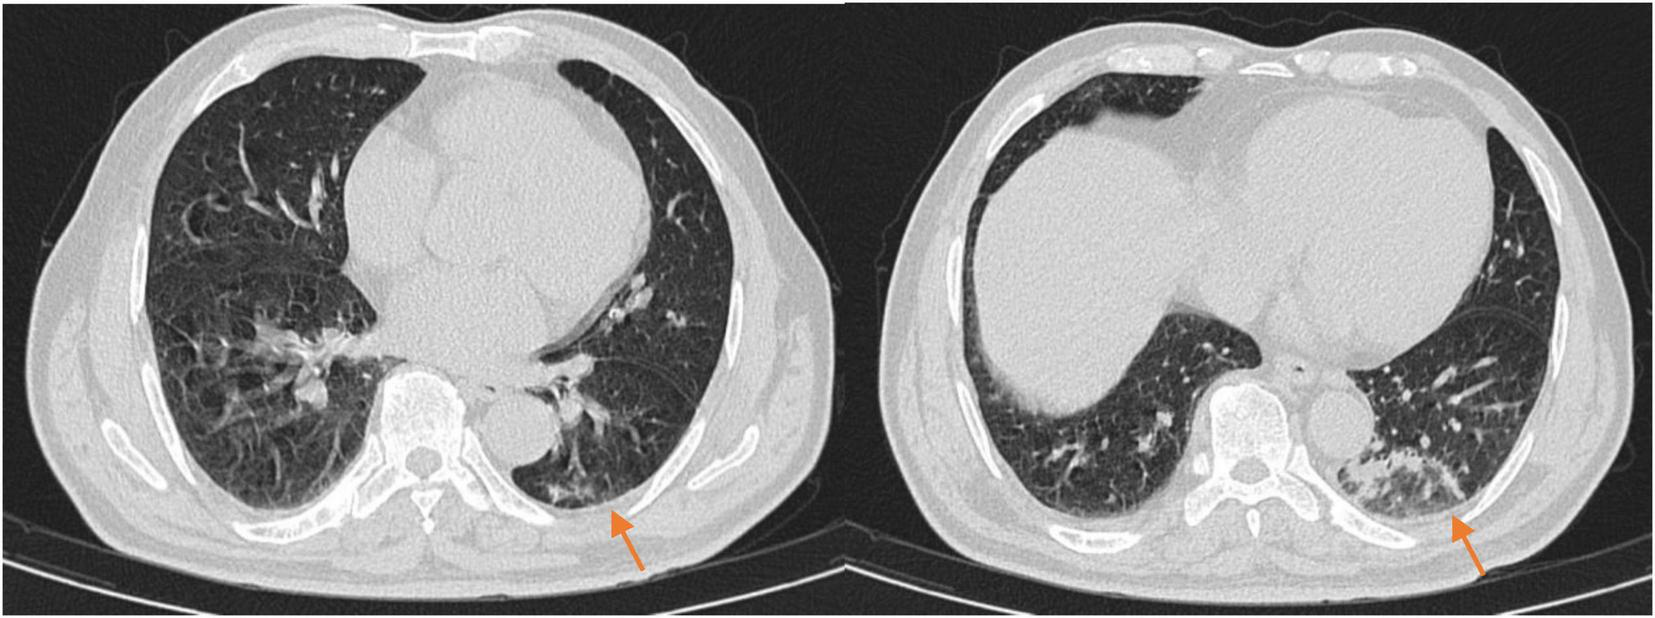

FIGURE 3

The chest CT on reexamination (2025-02-23) showed a high-density shadow in the left lower lobe, with a significantly reduced area compared to the previous scan.

On the 10th day of treatment, a recheck of chest CT showed significant absorption of the infection focus compared to previous scans (Figure 3), and all laboratory parameters have normalized (Table 1). The patient was discharged on day 11 after significant improvement. After discharge, the patient continued oral omadacycline (300 mg once daily) for 5 days before discontinuing the medication (Figure 2): a follow-up was conducted 1 month after discharge, and the patient’s symptoms had completely resolved. A repeat chest CT showed significant absorption of the exudates (Figure 4).